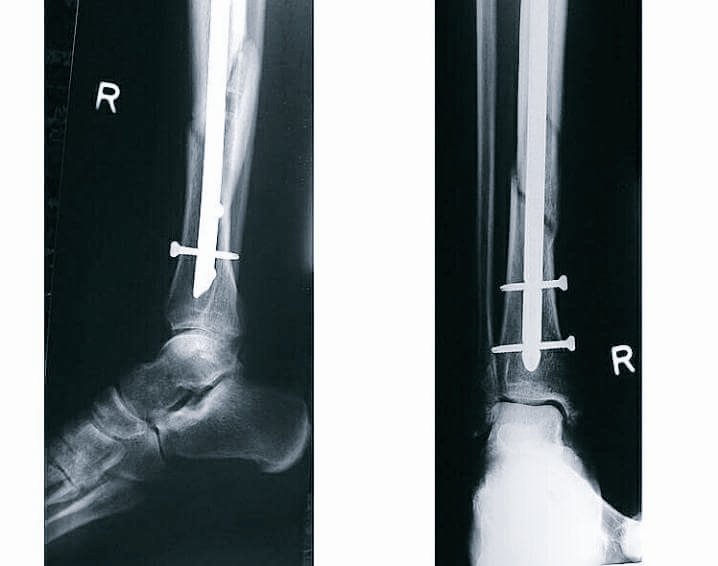

Pembalap Yamaha Movistar Valentino Rossi ternyata minta pulang lebih cepat dari rumah sakit setelah menghabiskan hanya satu malam di ‘Azienda Ospedaliero-Universitaria Ospedali Riuniti’ di Ancona, setelah menjalani operasi yang dilakukan akibat patah tulang pada kaki kanannya, dikabarkan kondisi Valentino Rossi cukup membaik sehingga dia bisa meninggalkan rumah sakit.

Berikut Foto-Foto Valentino Rossi saat dirawat dan ketika pulang ke rumah: